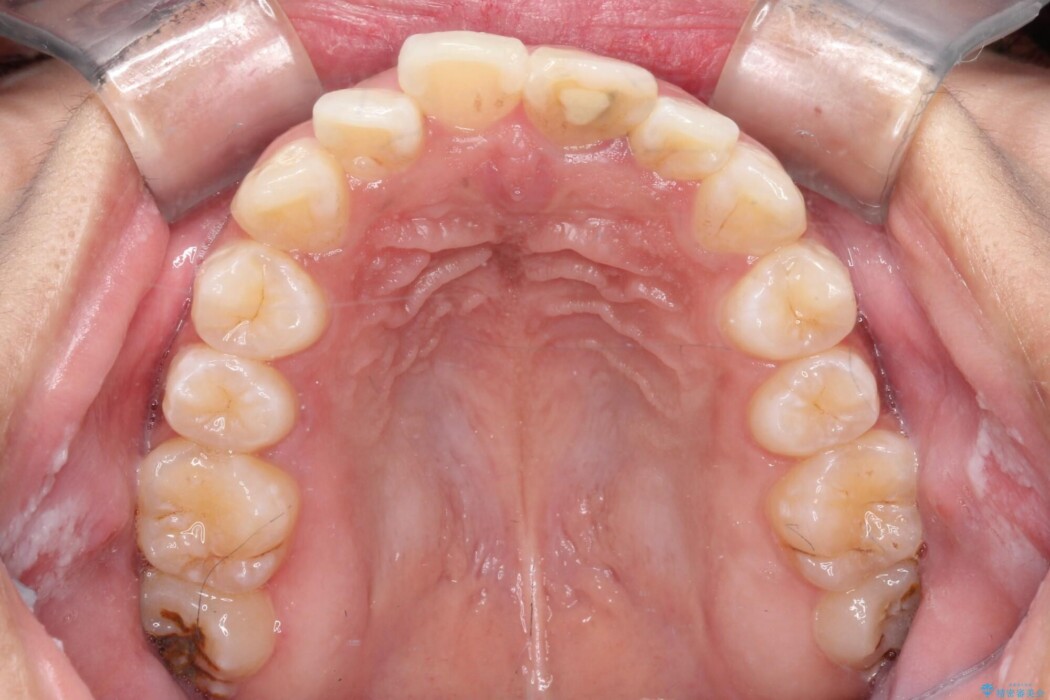

矯正検査の結果、歯列全体のスペースが不足しており、これが突出感の原因となっていました。

無理に歯を並べても口元の突出感は解消されないため、上下左右4番を抜歯しスペースを確保、目立ちにくい審美ワイヤー装置にて治療を行うこととしました。